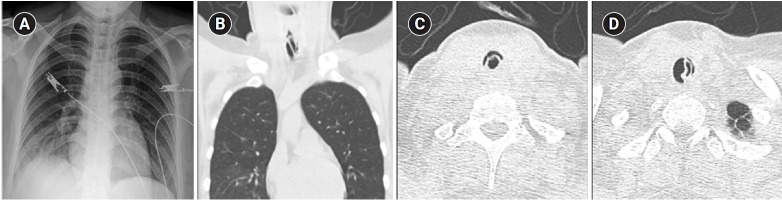

Young woman with recurrent paroxysmal stridor after extubation.